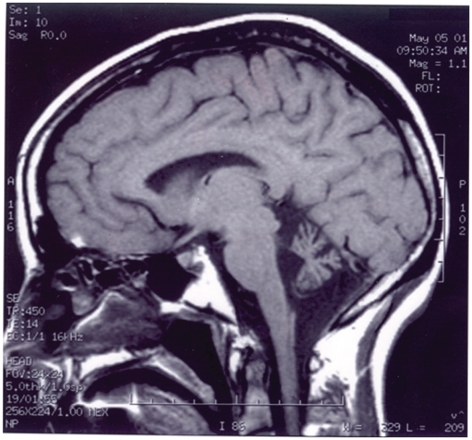

Figure 2. MRI of Patient with the p.Arg423His mutation.Cerebellar atrophy in a 48 year old female (H2591) with ataxia and the KCNC3Arg423His mutation. Midsagittal T1-weighted MRI of the brain shows a small atrophic cerebellum with a normal appearing brainstem.